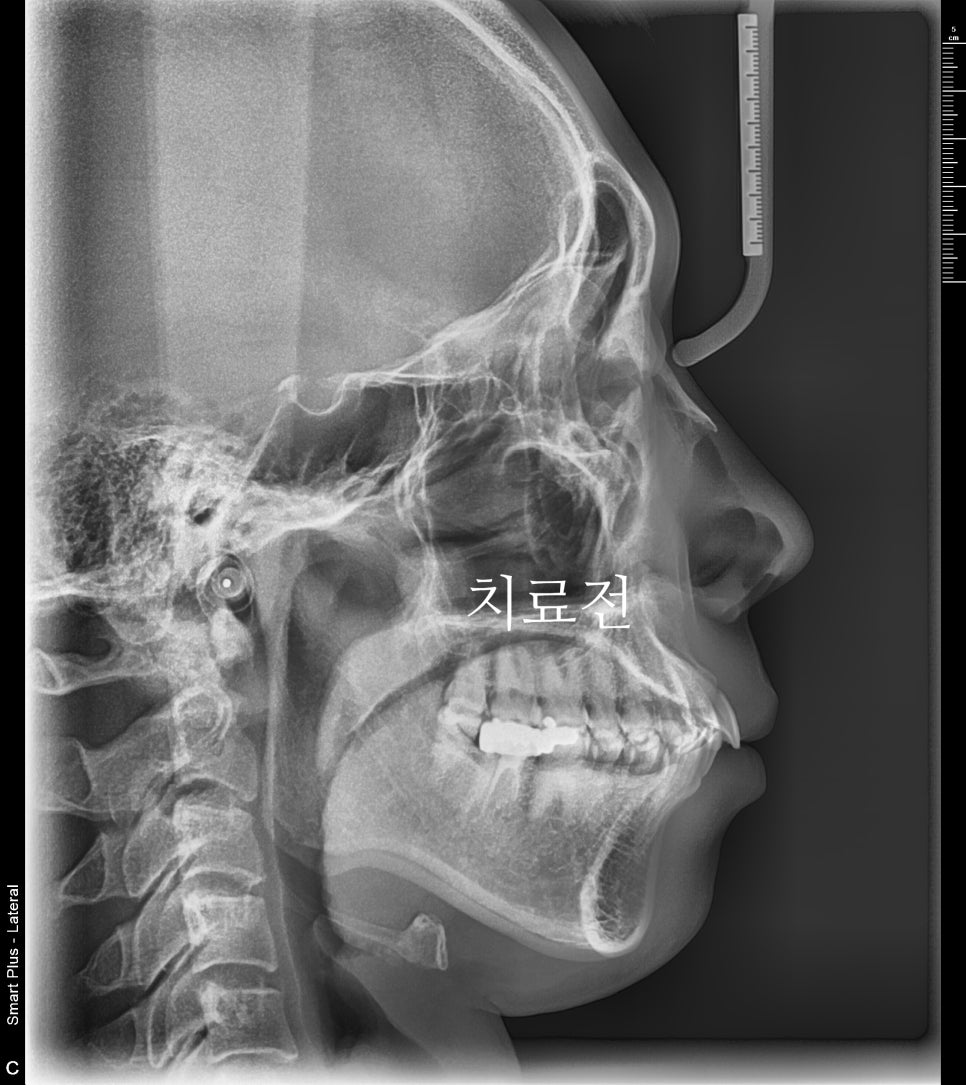

치료전과 후의 엑스레이 입니다.

악궁의 확장을 통한 앞니의 후방이동도 최대한 이루어냈습니다.